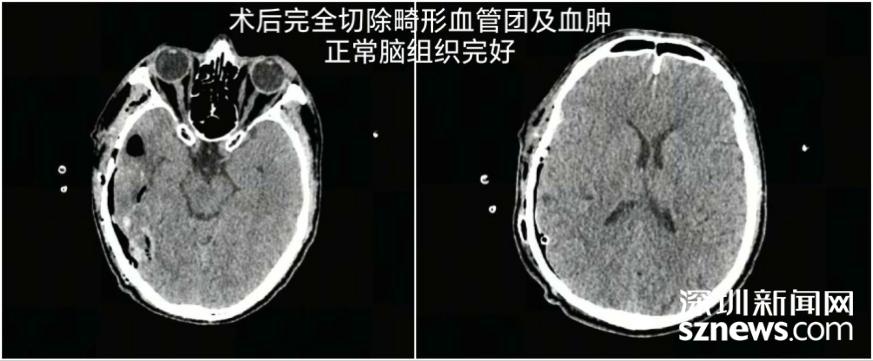

千钧一发之际,神经外科手术团队火速响应,迅速启动急救绿色通道。无影灯下,一场与死神的较量正式拉开帷幕。鲁春鹤主任带领团队,化身“拆弹专家”,凭借精湛的医术和丰富的经验,在复杂的脑血管结构中“抽丝剥茧”,精准定位畸形血管团。手术全程分秒必争,每一个操作都力求极致,完整切除畸形血管团、彻底清除血肿,成功拆除这颗致命“炸弹”。术后24小时,患者奇迹般清醒,各项生命体征逐渐平稳,成功重获新生。